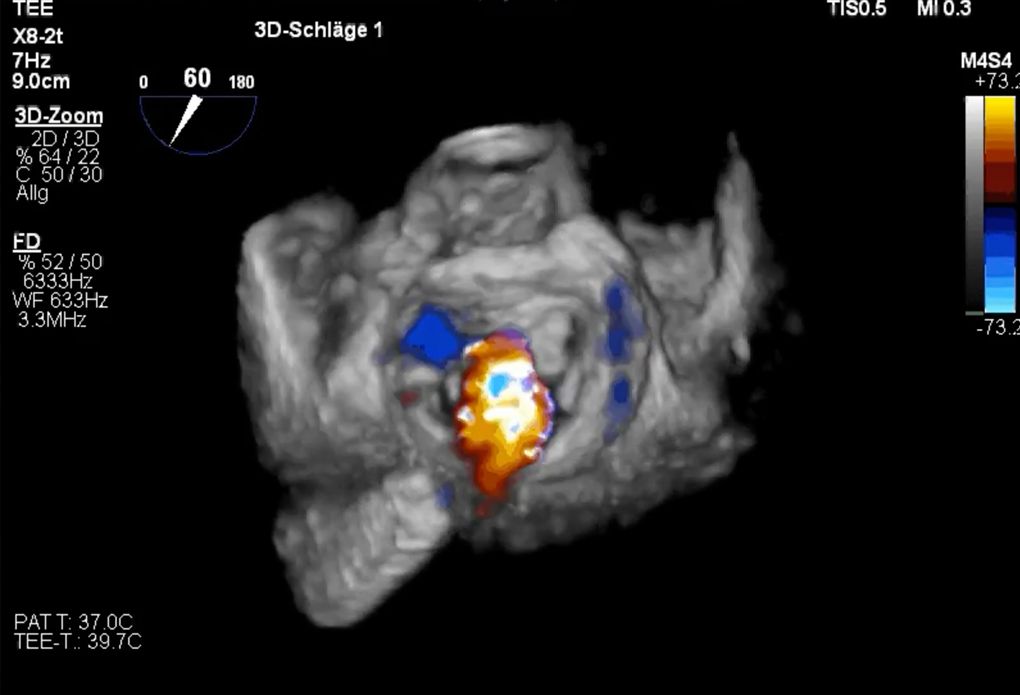

Die Mitralklappensegel werden bei diesem Eingriff mittels Kathetertechnik an der undichten Stelle mit einer Klammer (Clip; MitraClip- oder Pascal-System) „zusammengeheftet“, wodurch aus der einen undichten Öffnung zwei gut schließende Klappenöffnungen werden.